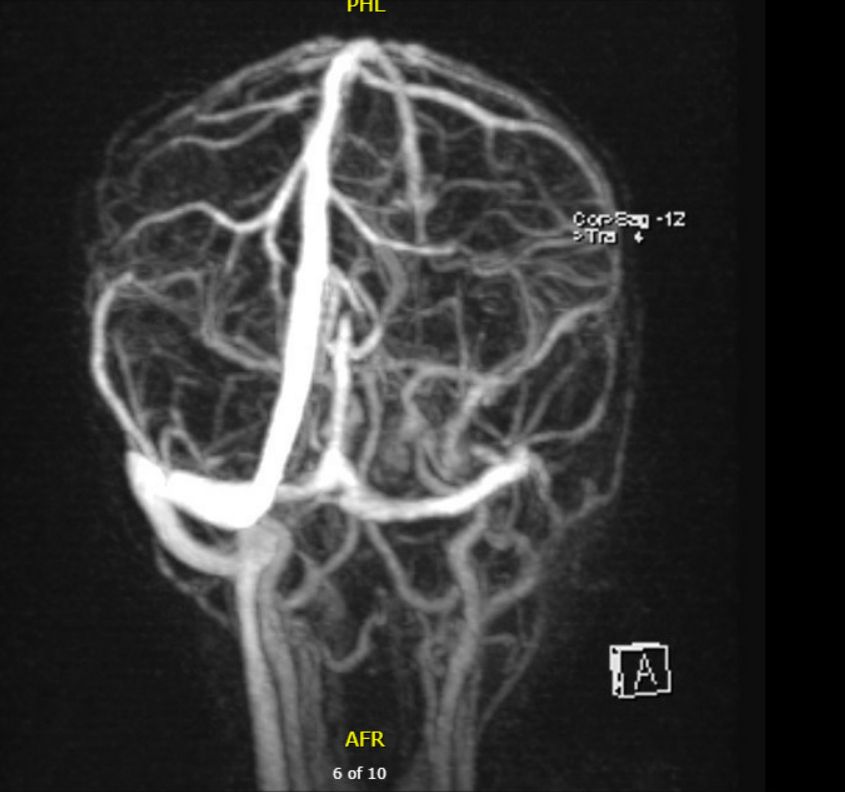

Case Summary: In less than 400 words, please summarize the case. Briefly describe the case and any particular complexities and/or complications encountered.: An unimmunized 18-month-old male presented with two days of fever to 106°F and seven days of foul-smelling left ear drainage. He had recently completed seven days of amoxicillin for left-sided acute otitis media. Initial workup revealed leukocytosis, thrombocytosis, elevated CRP, hyponatremia, and mildly elevated transaminases. A CT brain demonstrated left otitis externa with an adjacent periauricular abscess. Physical examination demonstrated purulent left ear drainage with postauricular swelling and erythema. He was started on empirical ceftriaxone and vancomycin. A CT of the temporal bones confirmed left otitis externa with an adjacent postauricular subperiosteal abscess and mastoiditis. He underwent a mastoidectomy and bilateral tympanostomy tube placement followed by clinical improvement. Five days later, he re-developed fever and had rising inflammatory markers. MRI/MRV brain revealed a cavernous sinus thrombosis extending to the internal jugular vein, consistent with Lemierre’s syndrome (LS). Enoxaparin was initiated for anticoagulation. Anaerobic cultures grew Fusobacterium necrophorum, and antibiotics were adjusted to ampicillin-sulbactam and metronidazole. He improved on 14 days of IV antibiotics followed by 14 days of oral amoxicillin-clavulanate.

Three weeks later, he had complete symptom resolution. MRI showed resolution of the subperiosteal abscess and improved sigmoid sinus and jugular bulb flow with residual chronic thrombus. Given the small size of the remaining thrombus, anticoagulation therapy was discontinued.